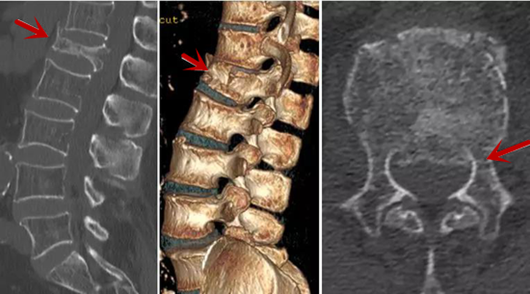

從左向右依次為CT矢狀位重建圖像、三維重建圖像、軸位掃描圖像,箭頭提示腰1椎體爆裂性骨折